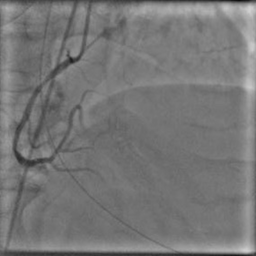

X-ray angiography is the most used imaging modality to visualise blood vessels for interventional purposes such as stenting of stenosed vessels or for diagnostic purposes such as assessment of myocardial perfusion or stenosis grading. To minimise ionising radiation exposure of the patient and medical personnel during image acquisition, low power X-Rays are used resulting in noisy and low contrast images. In the context of diagnosis, the main object of interest is the vascular tree, its branchings and variations in thickness. It is therefore necessary to accurately highlight the vessels in consecutive frames to reduce the noise and improve contrast. In addition, in interventional procedures, identifying interventional instruments (catheter, wires) is also needed in order to better plan and control their positioning. Efficiently discriminating between instruments and vessels as well as other anatomical structures that may have similar appearance is crucial during the interventions. Figure 1(a-c) shows an example of an angiogram sequence. Note large non-rigid motion between frames as well as the ambiguity between vessels and the catheter. Figure 1(e) shows a frame from a different sequence of the same patient but taken at different scan and angle and (f) shows a different patient. There is a significant difference in vessel as well as catheter locations in all three sequences, which we consider as independent examples. Figure 1(d) shows the ground truth segmentation of the first frame.

The dataset consists of anonymised fluoroscopy X-Rays of 26 different patients. The images were acquired during stent placement using a General Electric Innova 2000 system and stored according to standard medical protocol in DICOM format. In total the dataset includes 36000 frames corresponding to 365 distinct video sequences with an average of 98 frames each. Different sequences of the same patient were taken at different angles and stages of the procedure therefore they differ significantly as shown in Figure 1(c)(e)(f). Each frame is rescaled from to due to memory constraints.